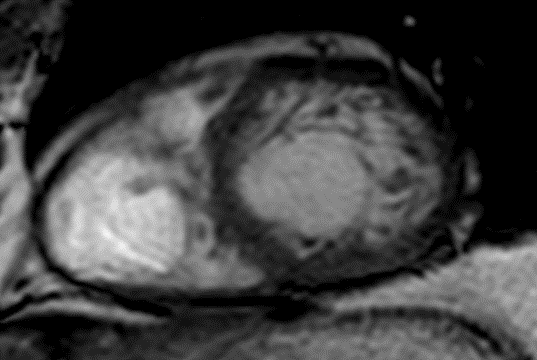

MRI Scan

Example showing increased trabecular muscle.